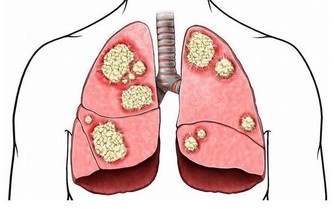

血管中的“臟東西”指的是甘油三酯、膽固醇,隨著人年齡的增大,這些“臟東西”會在血管壁上慢慢累積,導致血液流動受阻,這就是老年人更容易得腦血栓、心腦血管病、高血壓等疾病的原因。

血管堵塞的症狀

血管堵塞很危險,特別是中老年人群。小堵容易誘發中風,高血壓等疾病,而嚴重的堵塞會直接導致腦血栓、腦梗塞或直接猝死。所以在平時,清理血管很重要!